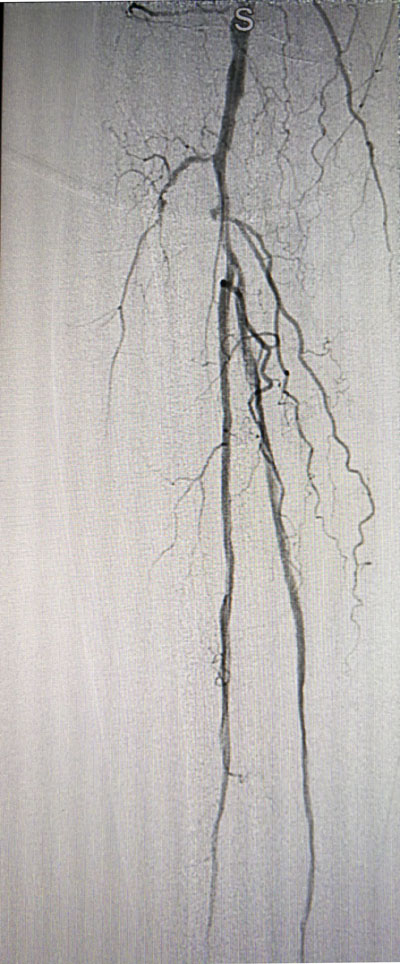

放射科导管室内做好了术前准备,患者由无创呼吸机及各种循环支持下开始介入手术,术中重症监护科严密观察患者的生命体征,内分泌科医生负责手术,患者下肢血流极差,膝下仅存一条多处严重狭窄的腓动脉供血,主要供血的胫前动脉及胫后动脉均长段闭塞,顺行穿刺成功后导丝下行困难,故采用踝下胫后动脉逆穿对接技术成功通过病变。经过近5个小时的奋斗,手术顺利完成,患者腓动脉及胫后动脉血流通畅,血流直达足底动脉环,患者感到足部逐渐温暖,术后清创时患者创面血流丰富。

治疗前

治疗后